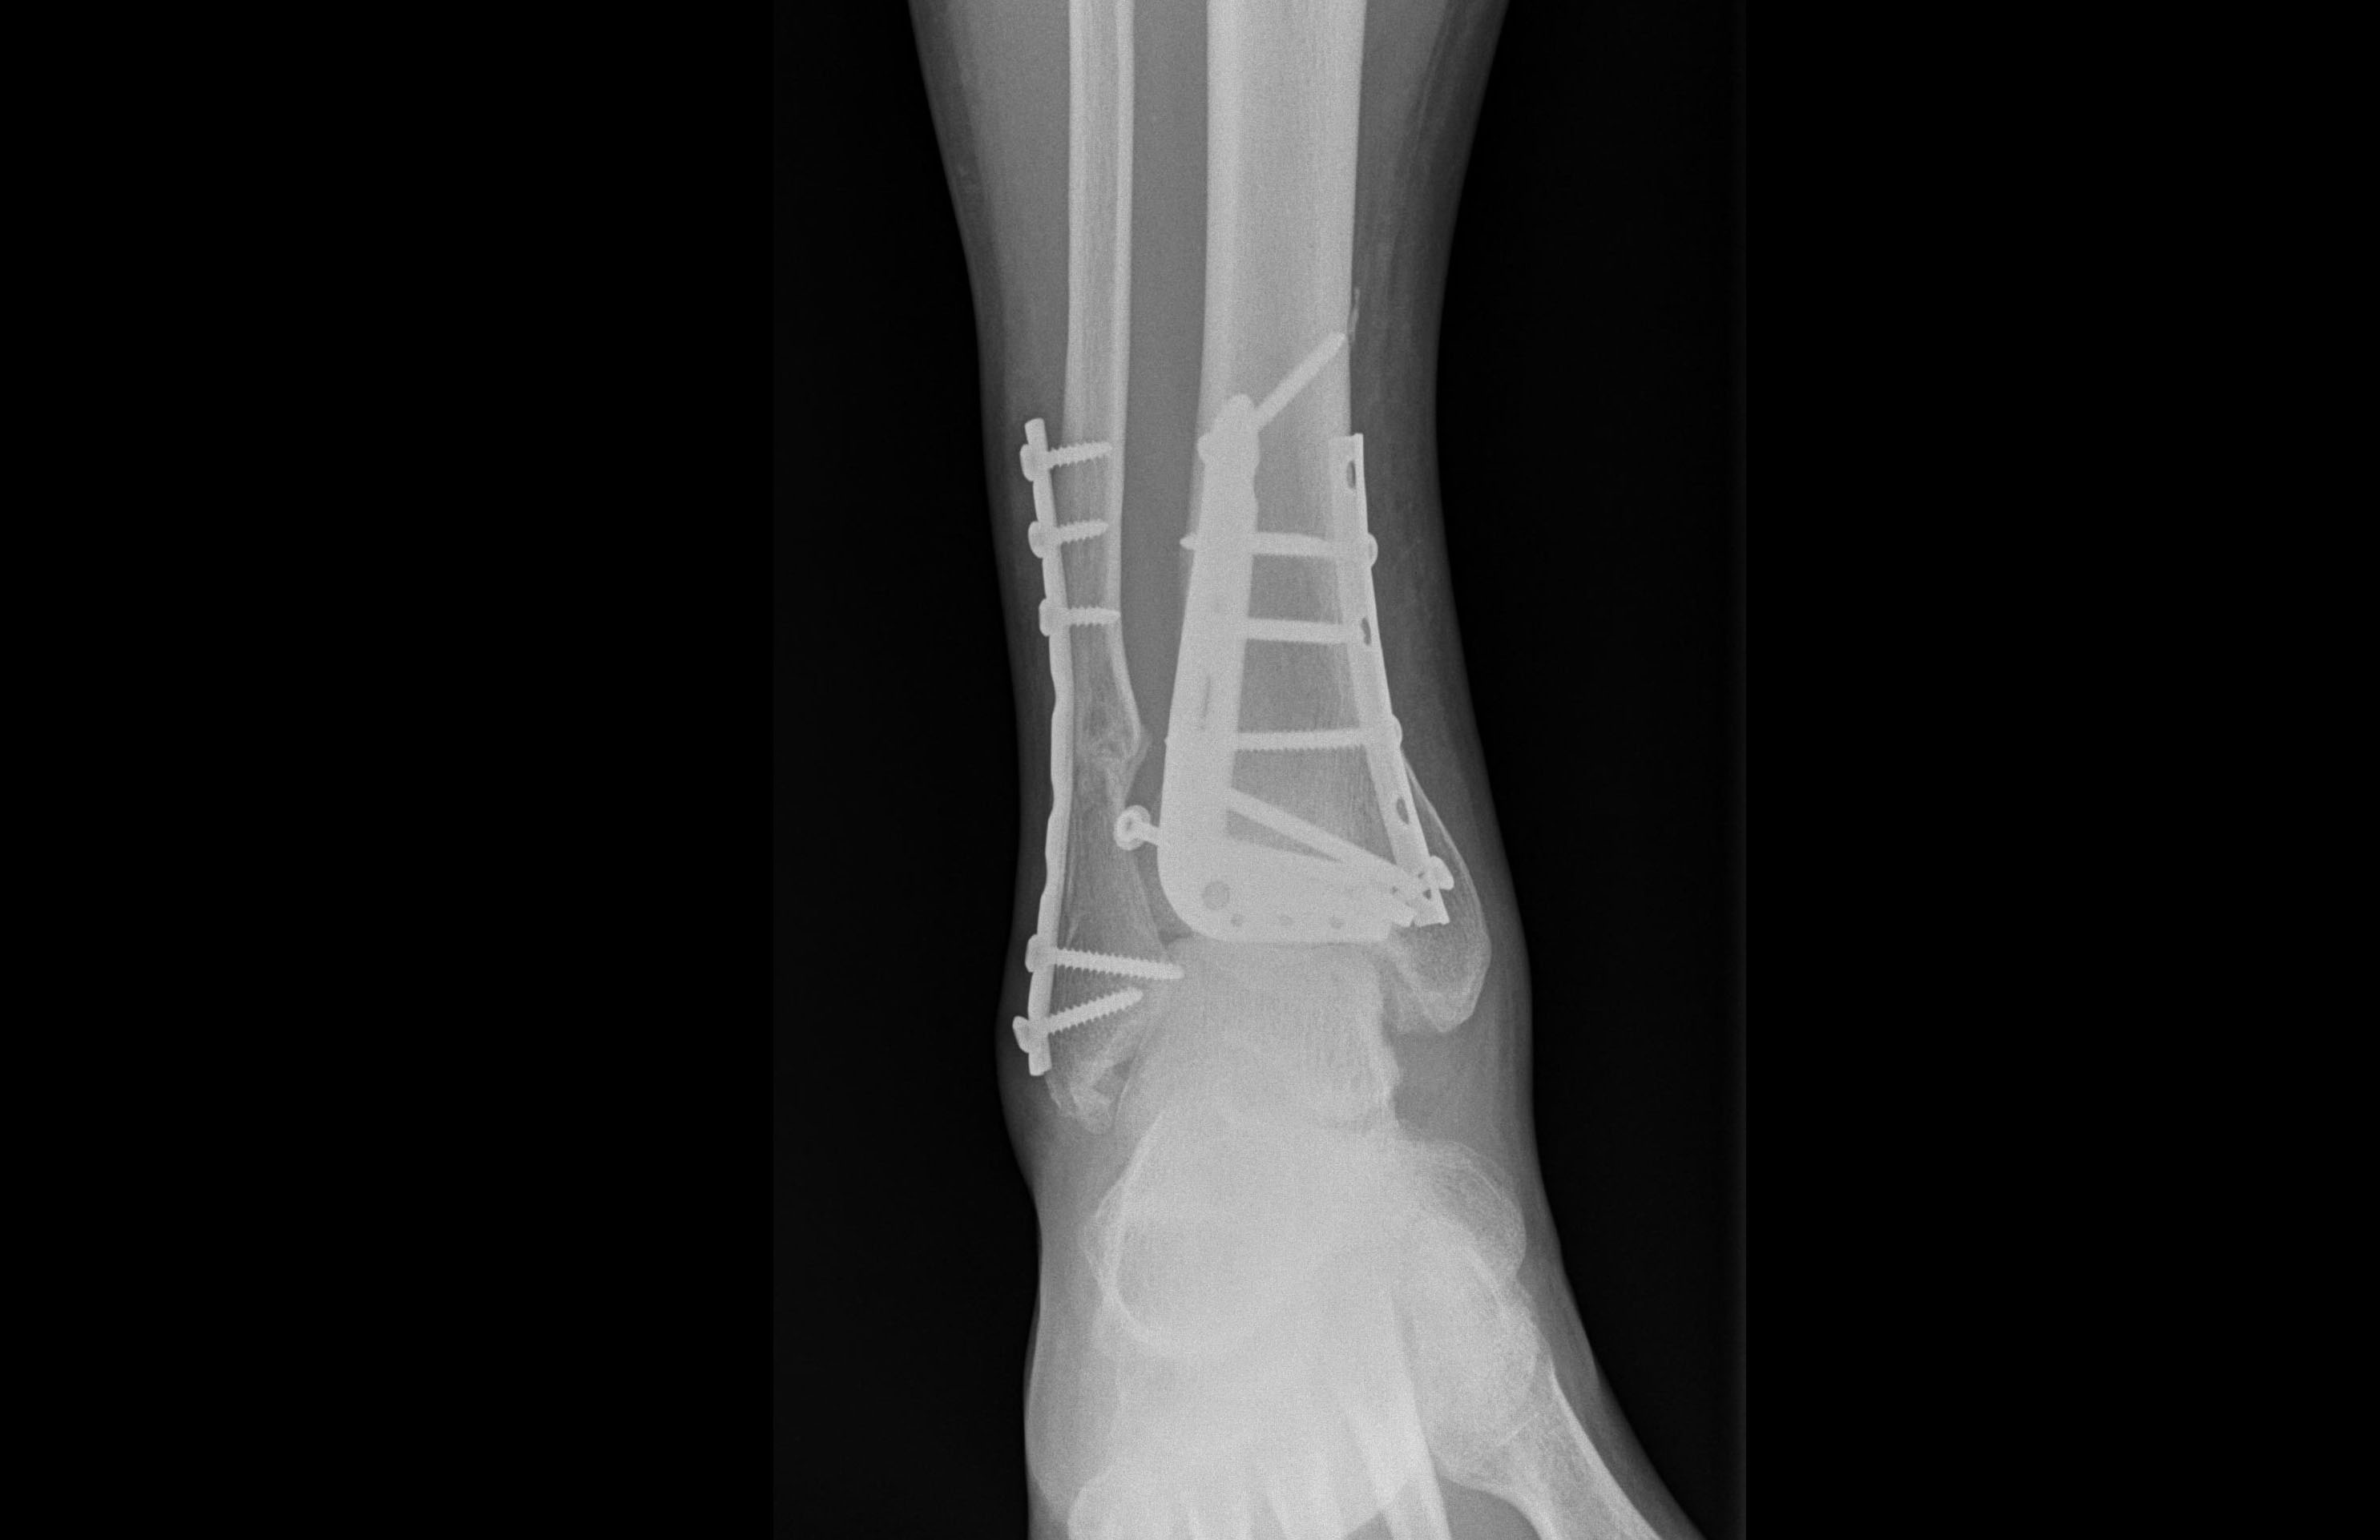

W przypadku większości operacji ortopedycznych stosuje się różne typy implantów, które mają na celu ustabilizowanie fragmentów kości, dopóki nie dojdzie do ich zrostu. Jeżeli użyte implanty wykonane są ze stali chirurgicznej, są przeciwwskazaniem do wykonania rezonansu magnetycznego tej okolicy ciała, a także niektórych zabiegów rehabilitacyjnych. Dodatkowo, zarówno implanty stalowe, jak i tytanowe mogą powodować miejscowe podrażnienia tkanek miękkich, np. skóry znajdującej się nad implantem. W takim przypadku konieczne jest usunięcie implantów. Najczęściej dokonuje się go przynajmniej 6 miesięcy od pierwotnej operacji, aby mieć pewność obecności zrostu kostnego.